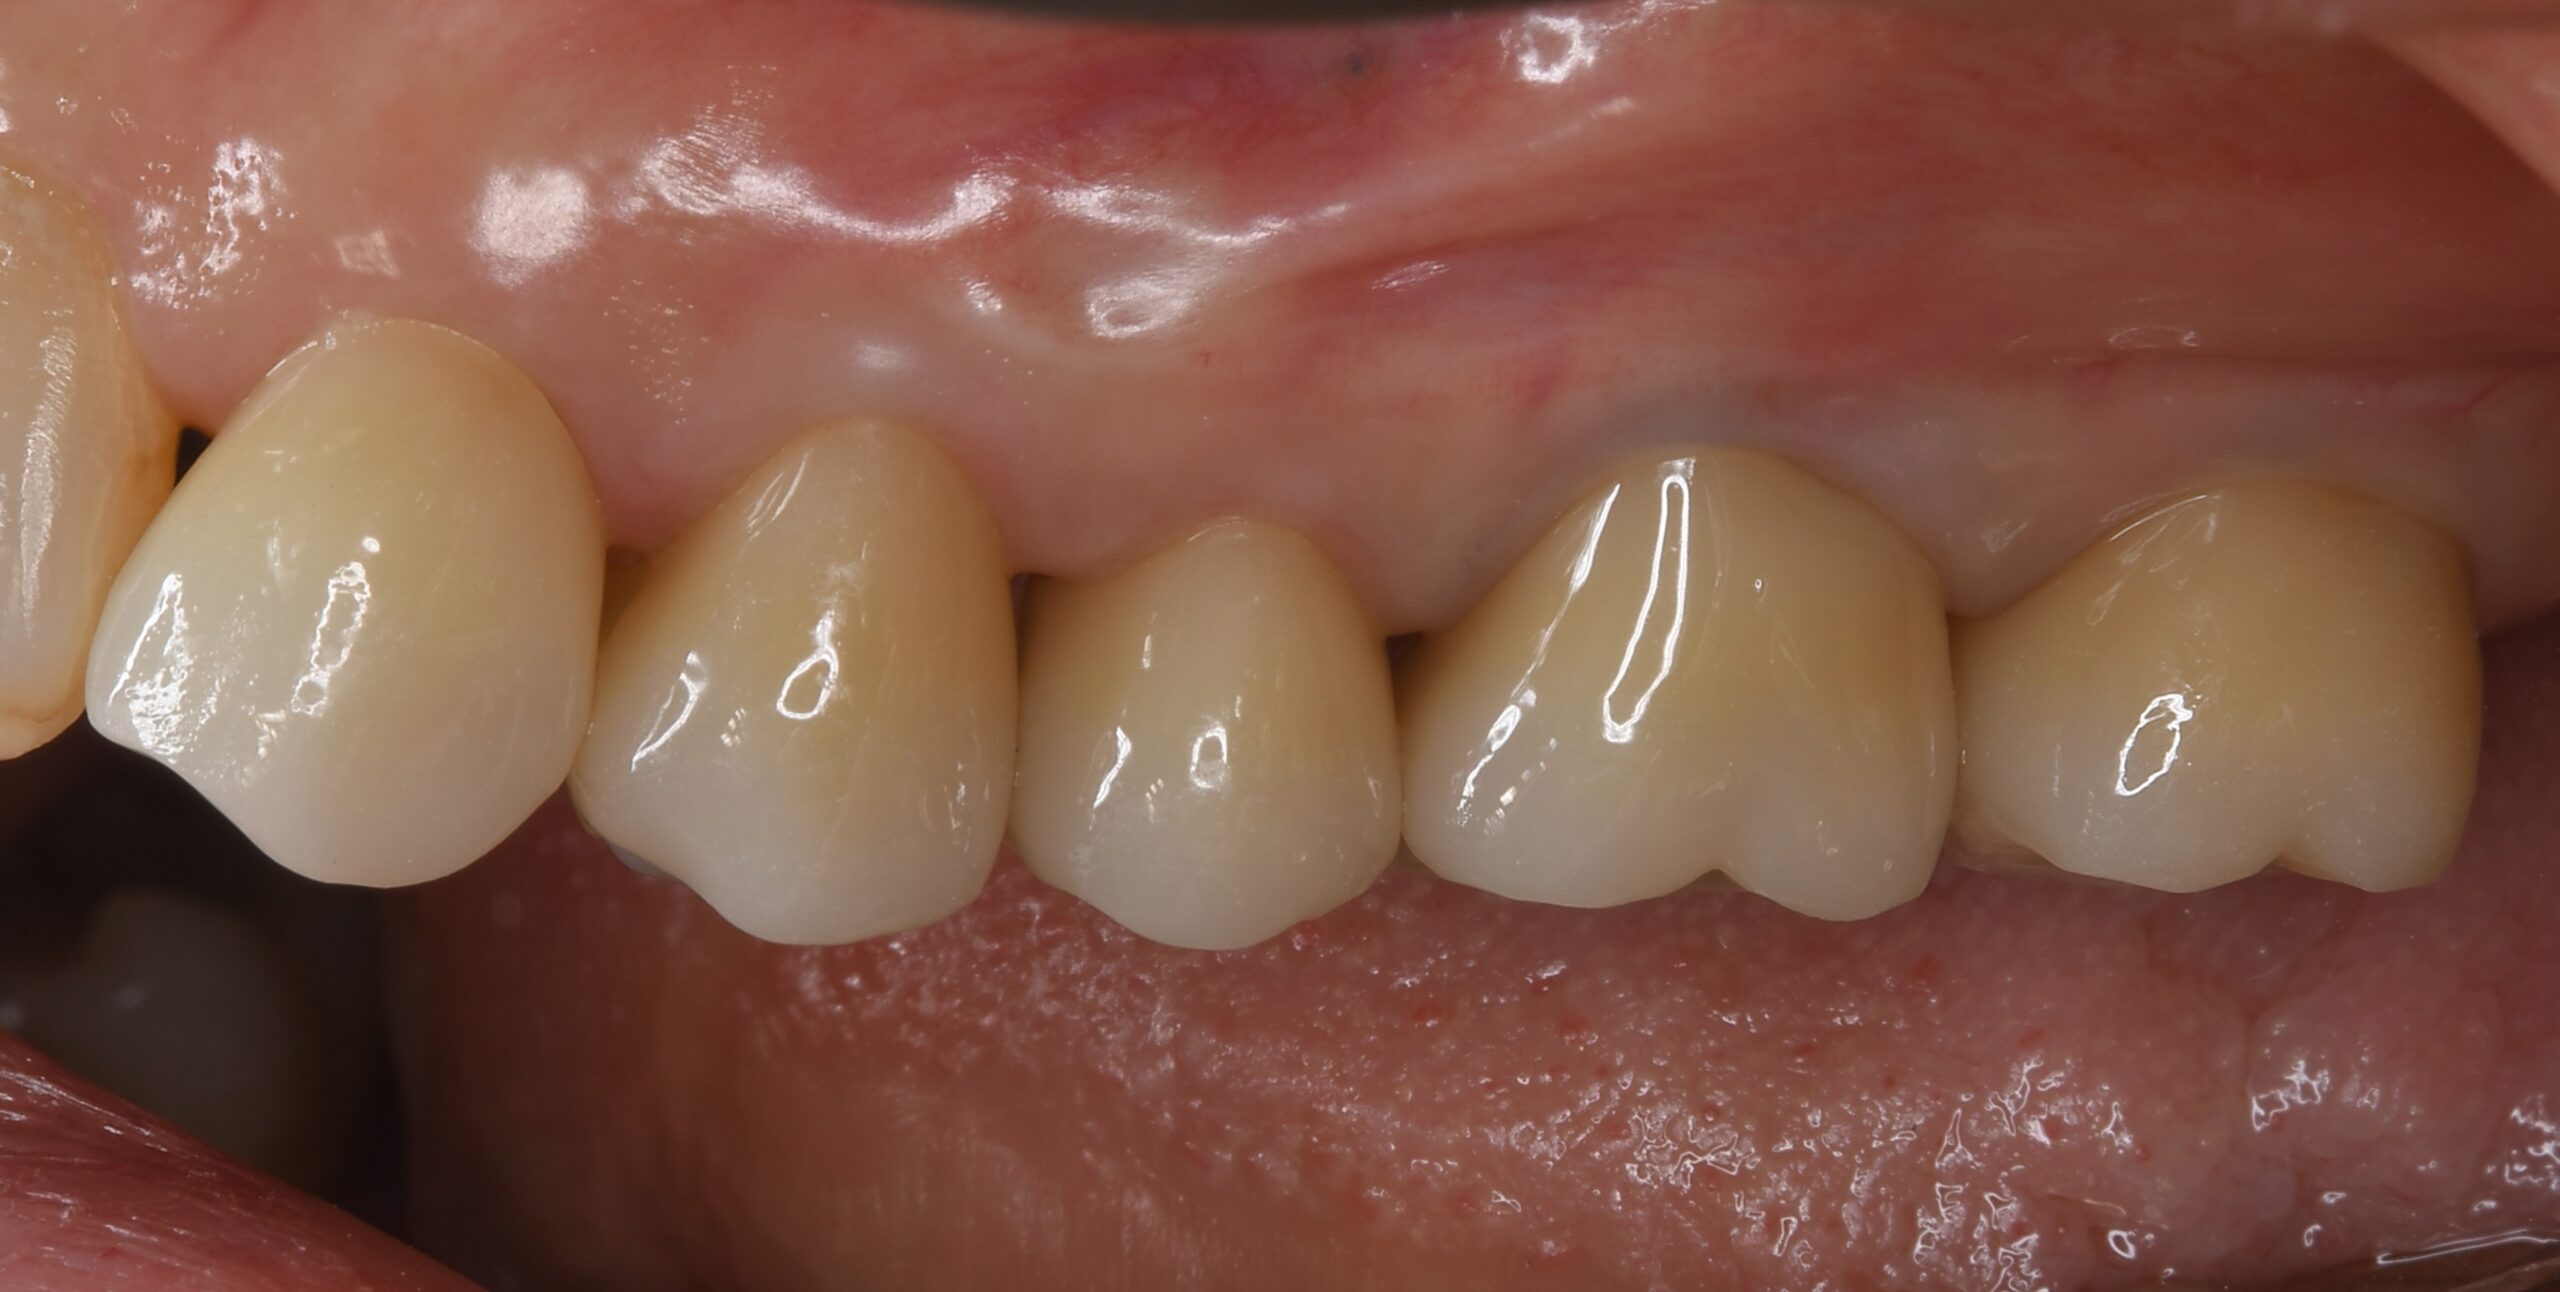

| 患者様データ | 60代 女性 |

| 来院時の主訴 | 「左上の歯が噛むと違和感がある。」 |

| 医院の診断 | 虫歯の再発、重度の歯周病を併発した慢性根尖性歯周炎 |

一般的に歯周病と根尖病変の混合病変は非常にシビアな状態と言われています。 この患者様の場合、根管治療だけでは歯の保存は不可能だったため、一度歯を抜歯し綺麗にしてから戻す歯牙再植という手法を用いて歯の保存を試みました。患者様の日々の歯磨きの努力もあり、健全な状態に改善することができました。 |